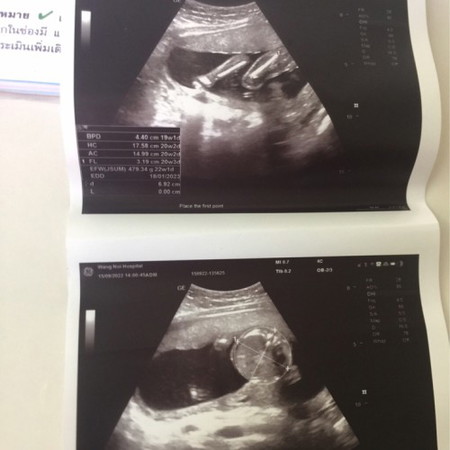

มันคือส่วนไหนของน้องคะ ดูไม่ออกเลย😅

ข้างบน : ขา ข้างล่าง : หัว ค่ะ